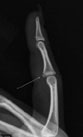

Choosing the right hand Therapist starts with them being able to read your X-rays and then fabricate the right brace for you. The therapists at Action Rehab Hand Therapy Clinic are experienced in assessing and reading X-rays.

Our therapists do regular GP and Emergency Doctor training and can advise on the most appropriate action for your Fractured Finger treatment.